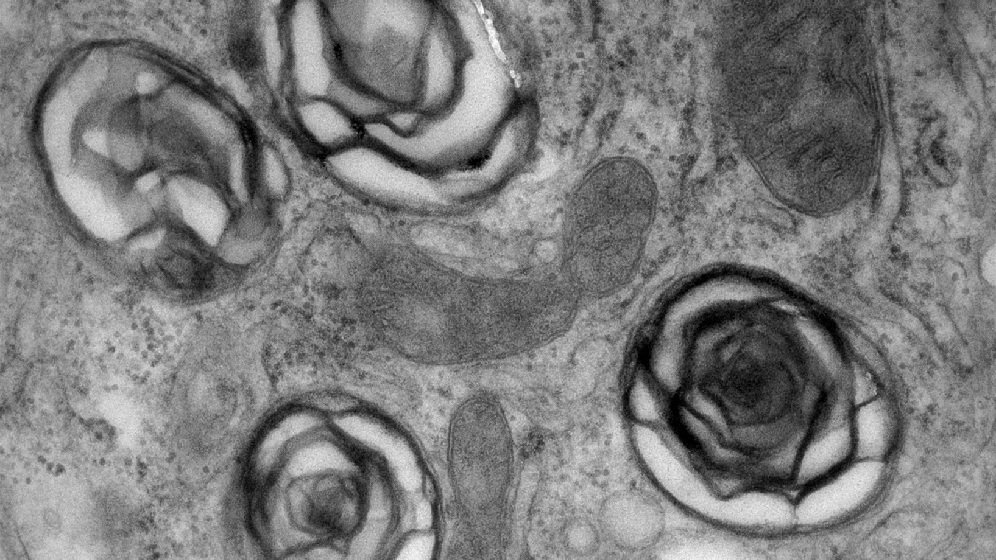

Diabetes Research - Autophagy

Our group aims to understand the functional impairment and survival of pancreatic beta-cells in type 2 diabetes. These beta-cells play a critical role in regulating blood glucose homeostasis. In particular, how autophagy, impacts on both beta-cell function and survival. We aim to identify target pathways for therapeutic intervention.

We are also exploring the complex interplay between nutrient sensing and autophagy. These areas are particularly relevant in type 2 diabetes. Illustrated by the loss of beta-cell function and increased cell death.